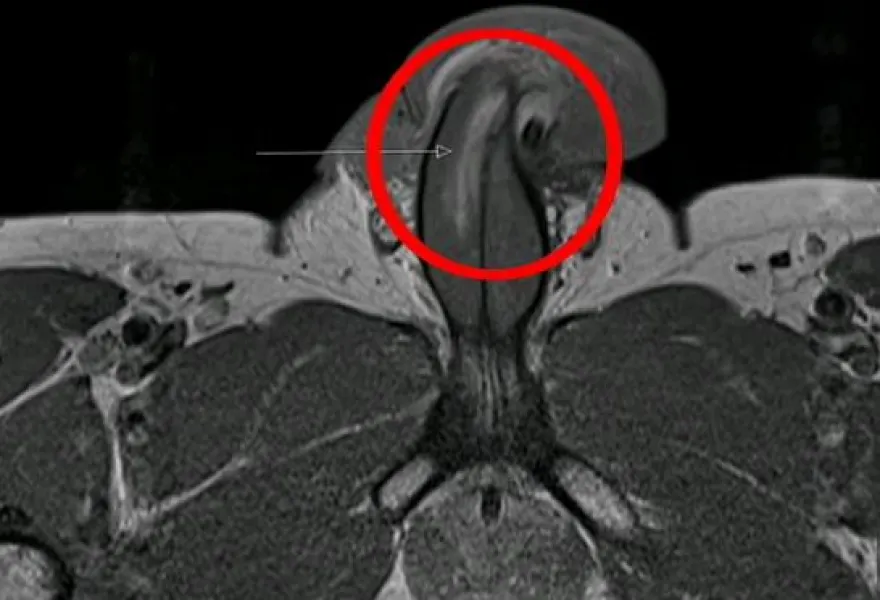

Κατά την διάρκεια της εξέτασης, οι γιατροί εντόπισαν μία ρωγμή τριών εκατοστών κατά μήκος της δεξιάς πλευράς του ανδρικού μορίου με την βοήθεια της μαγνητικής τομογραφίας, όπως αναφέρει η βρετανική εφημερίδα Daily Mail.

Τόνισαν επίσης ότι, όλα τα κατάγματα πέους που είχαν καταγραφεί μέχρι σήμερα ήταν οριζόντια.

Κατά την διείσδυση, το ανδρικό μόριο του 40χρονου άνδρα ράγισε.. και υπέστη κάταγμα μήκους τριών εκατοστών.